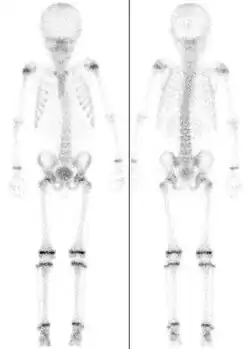

Für die Beurteilung auf Röntgenaufnahmen der am Handskelett des Menschen darstellbaren Epiphysenfugen gibt es spezielle Atlanten, die das chronologische Alter eines Kindes mit dem aktuellen Skelettalter vergleichen lassen (Abb.) Aufgrund der Vielzahl von Wachstumsfugen an den Handknochen, die sich alle zu unterschiedlichen Zeitpunkten knöchern verschließen, ist hier eine Zuordnung in Halbjahresschritten möglich.[4] Damit können, zusammen mit aktuellen Längenmessungen von Körpergröße, Sitzgröße, Beinlänge etc., Aussagen über das noch zu erwartende Gesamtwachstum des Kindes oder des Jugendlichen gemacht werden. Aufgrund der unterschiedlichen Geschlechtsentwicklung bei Mädchen und Jungen ist der Reifungsprozess und damit das Skelettwachstum bei Mädchen früher abgeschlossen. Die ersten Epiphysenfugen schließen sich bei Mädchen um das 14. Lebensjahr, die letzten Fugen beim Jungen nach dem neunzehnten Lebensjahr.

Untersuchungen von Röntgenaufnahmen von zwischen 1915 und 2006 geborenen Kindern haben gezeigt, dass sich der Zeitpunkt, an dem sich die Wachstumsfugen schließen, im Verlauf des letzten Jahrhunderts immer weiter vorverlegt hat und damit – ähnlich wie auch die Pubertät – immer früher eintritt. Der Grund dafür ist nicht ersichtlich.[5]